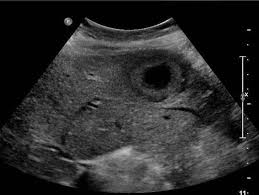

복부 초음파는 비침습적이며 방사선 노출이 없는 안전한 검사 방법으로, 초음파(ultrasound)를 통해 복부 내 장기들의 상태를 실시간으로 확인할 수 있는 진단 도구입니다. 복부 초음파로 알 수 있는 것 중에서는 특히 간, 담낭, 췌장, 비장, 신장, 방광, 대동맥, 소장, 대장 등의 상태를 파악할 수 있으며, 질환의 조기 발견에 탁월한 효과를 보입니다.

- 간암, 간종양: 실질 내부에 덩어리 유무 탐색

- 신장 종양, 낭종: 악성·양성 종양 여부 1차 판별